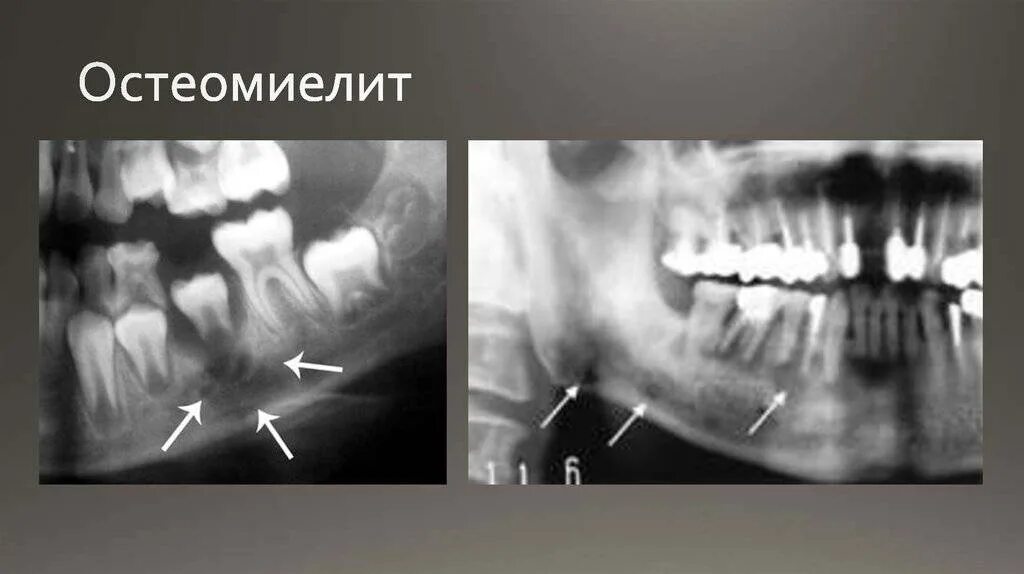

Подострая одонтогенного остеомиелита.. одонтогенный остеомиелит рентген. остеомиелит челюсти рентген. одонтогенный остеомиелит челюсти рентген.

Одонтогенный остеомиелит рентген. хронический остеомиелит челюсти. клиника острого остеомиелита нижней челюсти. муфтообразный инфильтрат.

Одонтогенный остеомиелит челюсти. остеомиелит верх челюсти. хронический остеомиелит челюсти снимок. одонтогенного остеомиелита челюстей.

Одонтогенного остеомиелита. одонтогенный остеомиелит нижнечелюстной. остеомиелит верхней челюсти кт. острый остеомиелит верхней челюсти.